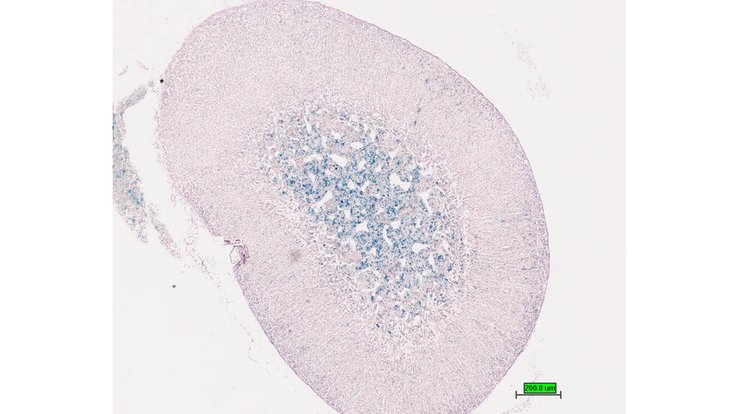

TS28: spleen Present UC Davis_1880927

Specimen UC Davis_1880928: postnatal adult; Ifngtm1.1(KOMP)Vlcg/Ifng+ (more )

Structure Level Pattern Image Note

TS28: spleen Present UC Davis_1880928

Specimen UC Davis_1880929: postnatal adult; Ifngtm1.1(KOMP)Vlcg/Ifng+ (more )

TS28: spleen Present UC Davis_1880929